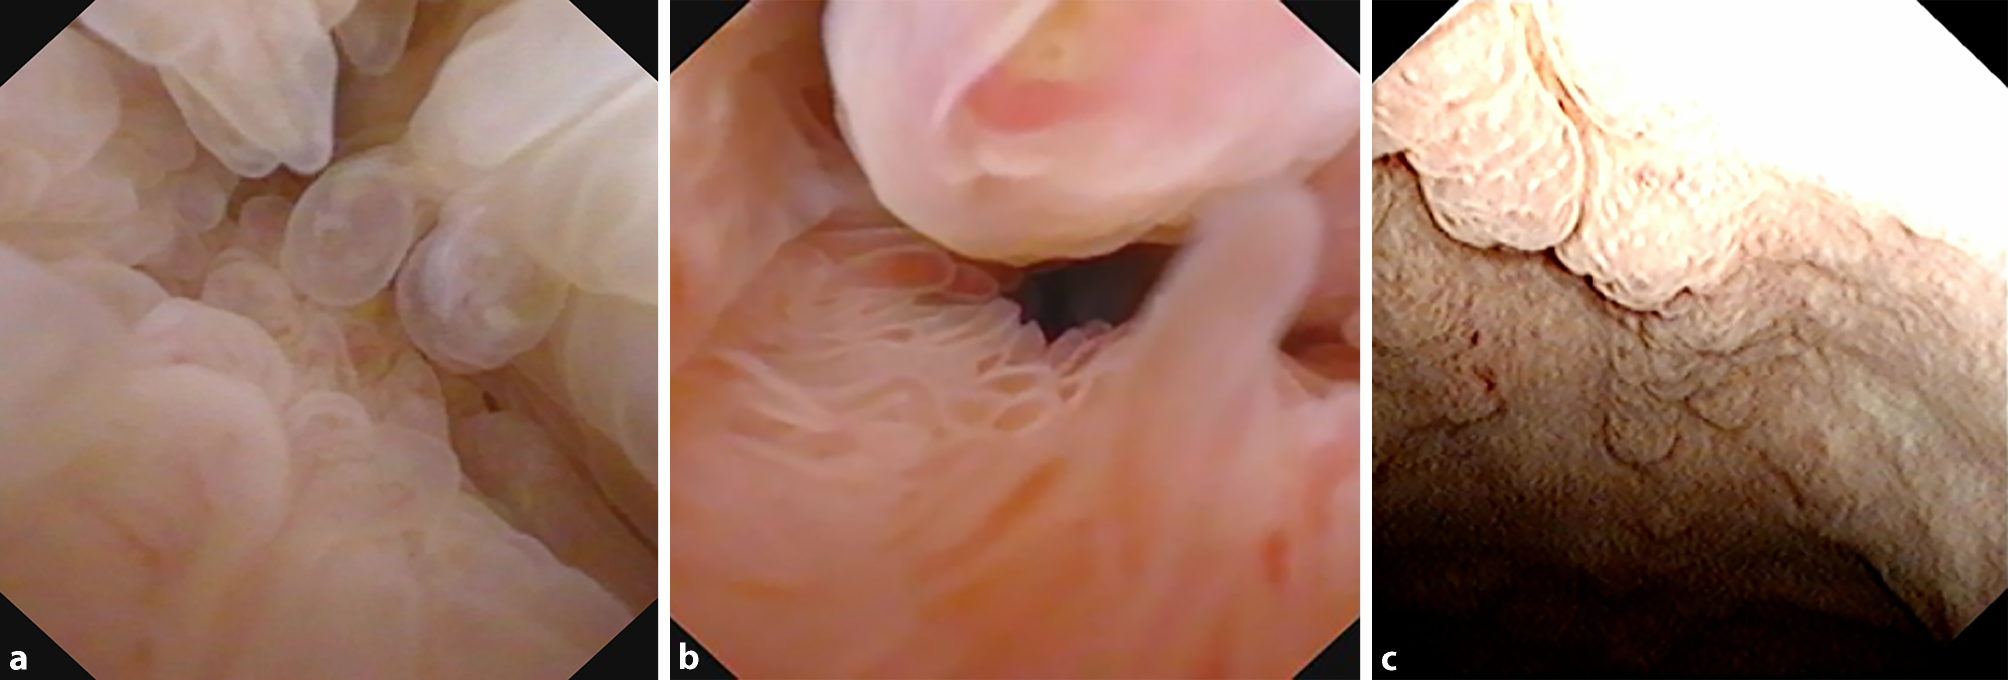

Bij cystoscopie wordt een eerste inschatting gemaakt van de macroscopische kenmerken. Cystitis glandularis komt het meest uitgesproken ter hoogte van het trigonum voor of in de urethra prostatica (zie fig. 1a en 1b), maar kan ook verspreid in blaas zichtbaar zijn (zie fig. 1c). Bij uitgebreide afwijkingen in de blaas dient de nierfunctie te worden bepaald en moet beeldvorming van de hoge urinewegen worden verricht. Als de nierfunctie het toelaat, kan een CT-scan met uitscheidingsfase een beeld geven van zowel de mate als de oorzaak van de hydronefrose, als van de anatomische verhoudingen en eventuele mate van pelvic lipomatosis. Bij dit laatste wordt een peervormige blaas gezien (zie fig. 2a), met uitgesproken perirectale en perivesicale vetstructuren (zie fig. 2b). Deze vetstructuren kunnen ook leiden tot bilaterale hydronefrose en gemedialiseerde ligging van de distale ureteren. Afhankelijk van mate van hydronefrose en eventuele behandelconsequenties, kan de diagnostiek worden uitgebreid met een renogram.

Figuur 2

a Peervormige blaas. b Opvallend perirectaal vetweefsel